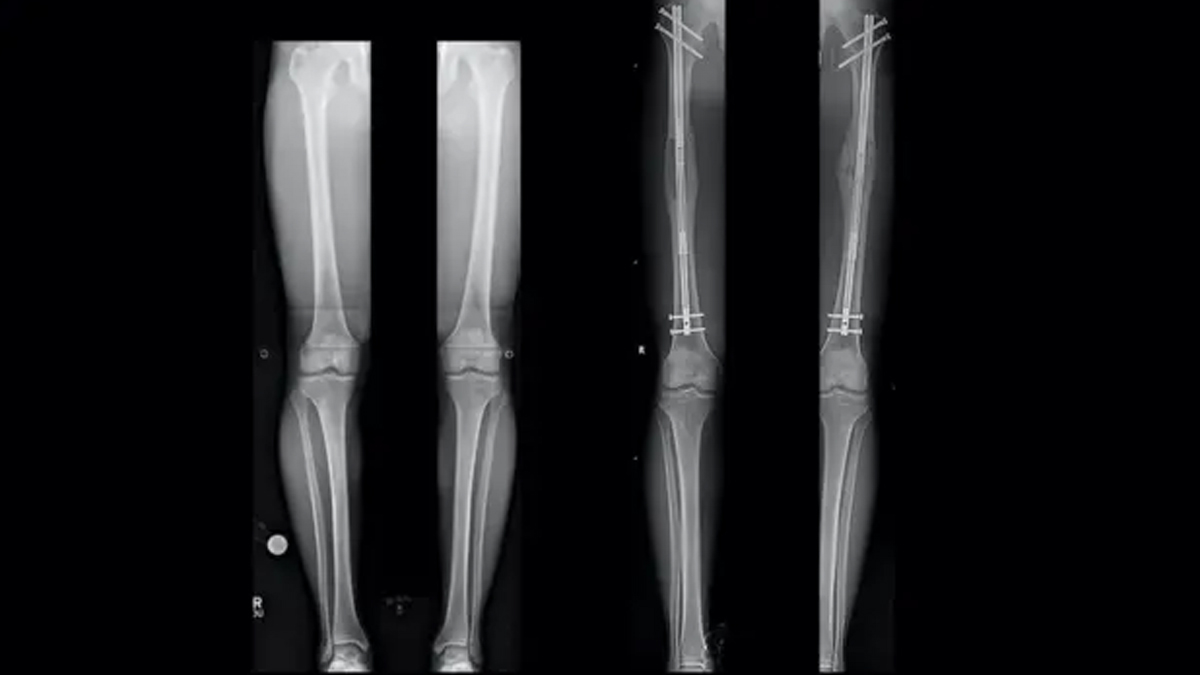

Leg-lengthening surgery was initially developed to assist individuals with a short or uneven limb due to injury, birth defect or disease. It is now also applied in cosmetic scenarios in which individuals want to appear taller.

According to Dr Anurag Das, Orthopaedic Surgeon, Orthopedics & Joint Replacement Department, CMRI Kolkata, it is a procedure that requires only the removal of one or several bones of the legs, most often the thigh bone (femur) or the shin bone (tibia), and then gradually pulling the broken parts apart. This pulling slowly encourages new bone to develop in the gap. The procedure is nearly akin to stretching your bones.

The special device is normally placed outside the leg or in the bone, the patient uses. The device works to ensure that each day, the grease between the bone segments is gradually expanded, which stimulates the growth of new bone and soft tissues such as muscles and skin to stretch and grow with time.